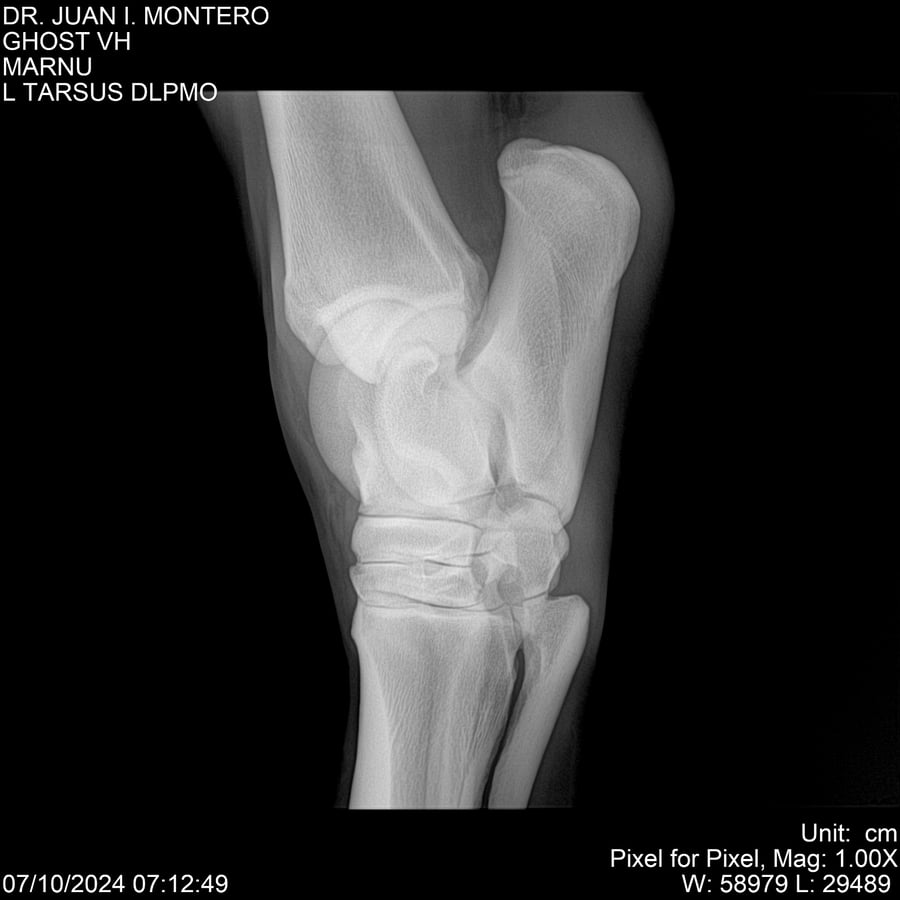

LOTE 15, GHOST VH 🔥 🔥 🔥 Lote Anterior Volver al remate Lote Siguiente Ficha Contacto Montevideo - Ficha del Lote Identificador: #282525 Categoría: Yeguarizos Montevideo - 69 Visualizaciones ClicData Contacto Empresa: Abelenda N. R., Walter Hugo Nombre*: Teléfono* : E-mail* : Mensaje Enviar Registrese gratis Este contenido Exclusivo está disponible sólo para usuarios registrados Ingresar